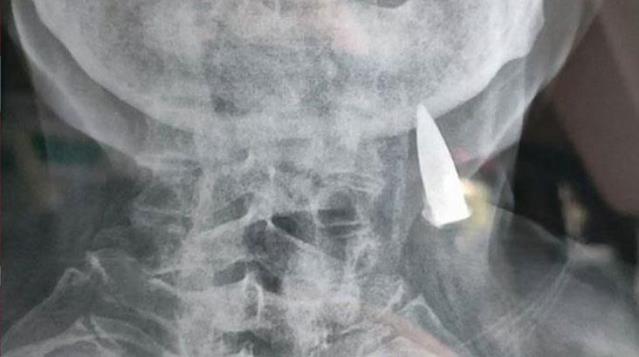

95 yaşlı Zhao He adlı şəxsin boynunda güllə aşkarlanıb.

25 yaşında ikən Çinin lehinə İkinci Dünya Müharibəsində döyüşərkən çoxlu güllə yarası alan Zhao He, daha sonra bədənindəki bütün güllələrin çıxarıldığını sanıb.

95 yaşında artan baş ağrıları nəticəsində isə o gerçəyi öyrənib. 70 il sonra boynunda qalan güllənin çıxarılmasını isə qəbul etməyərək, onunla ölmək istədiyini deyib